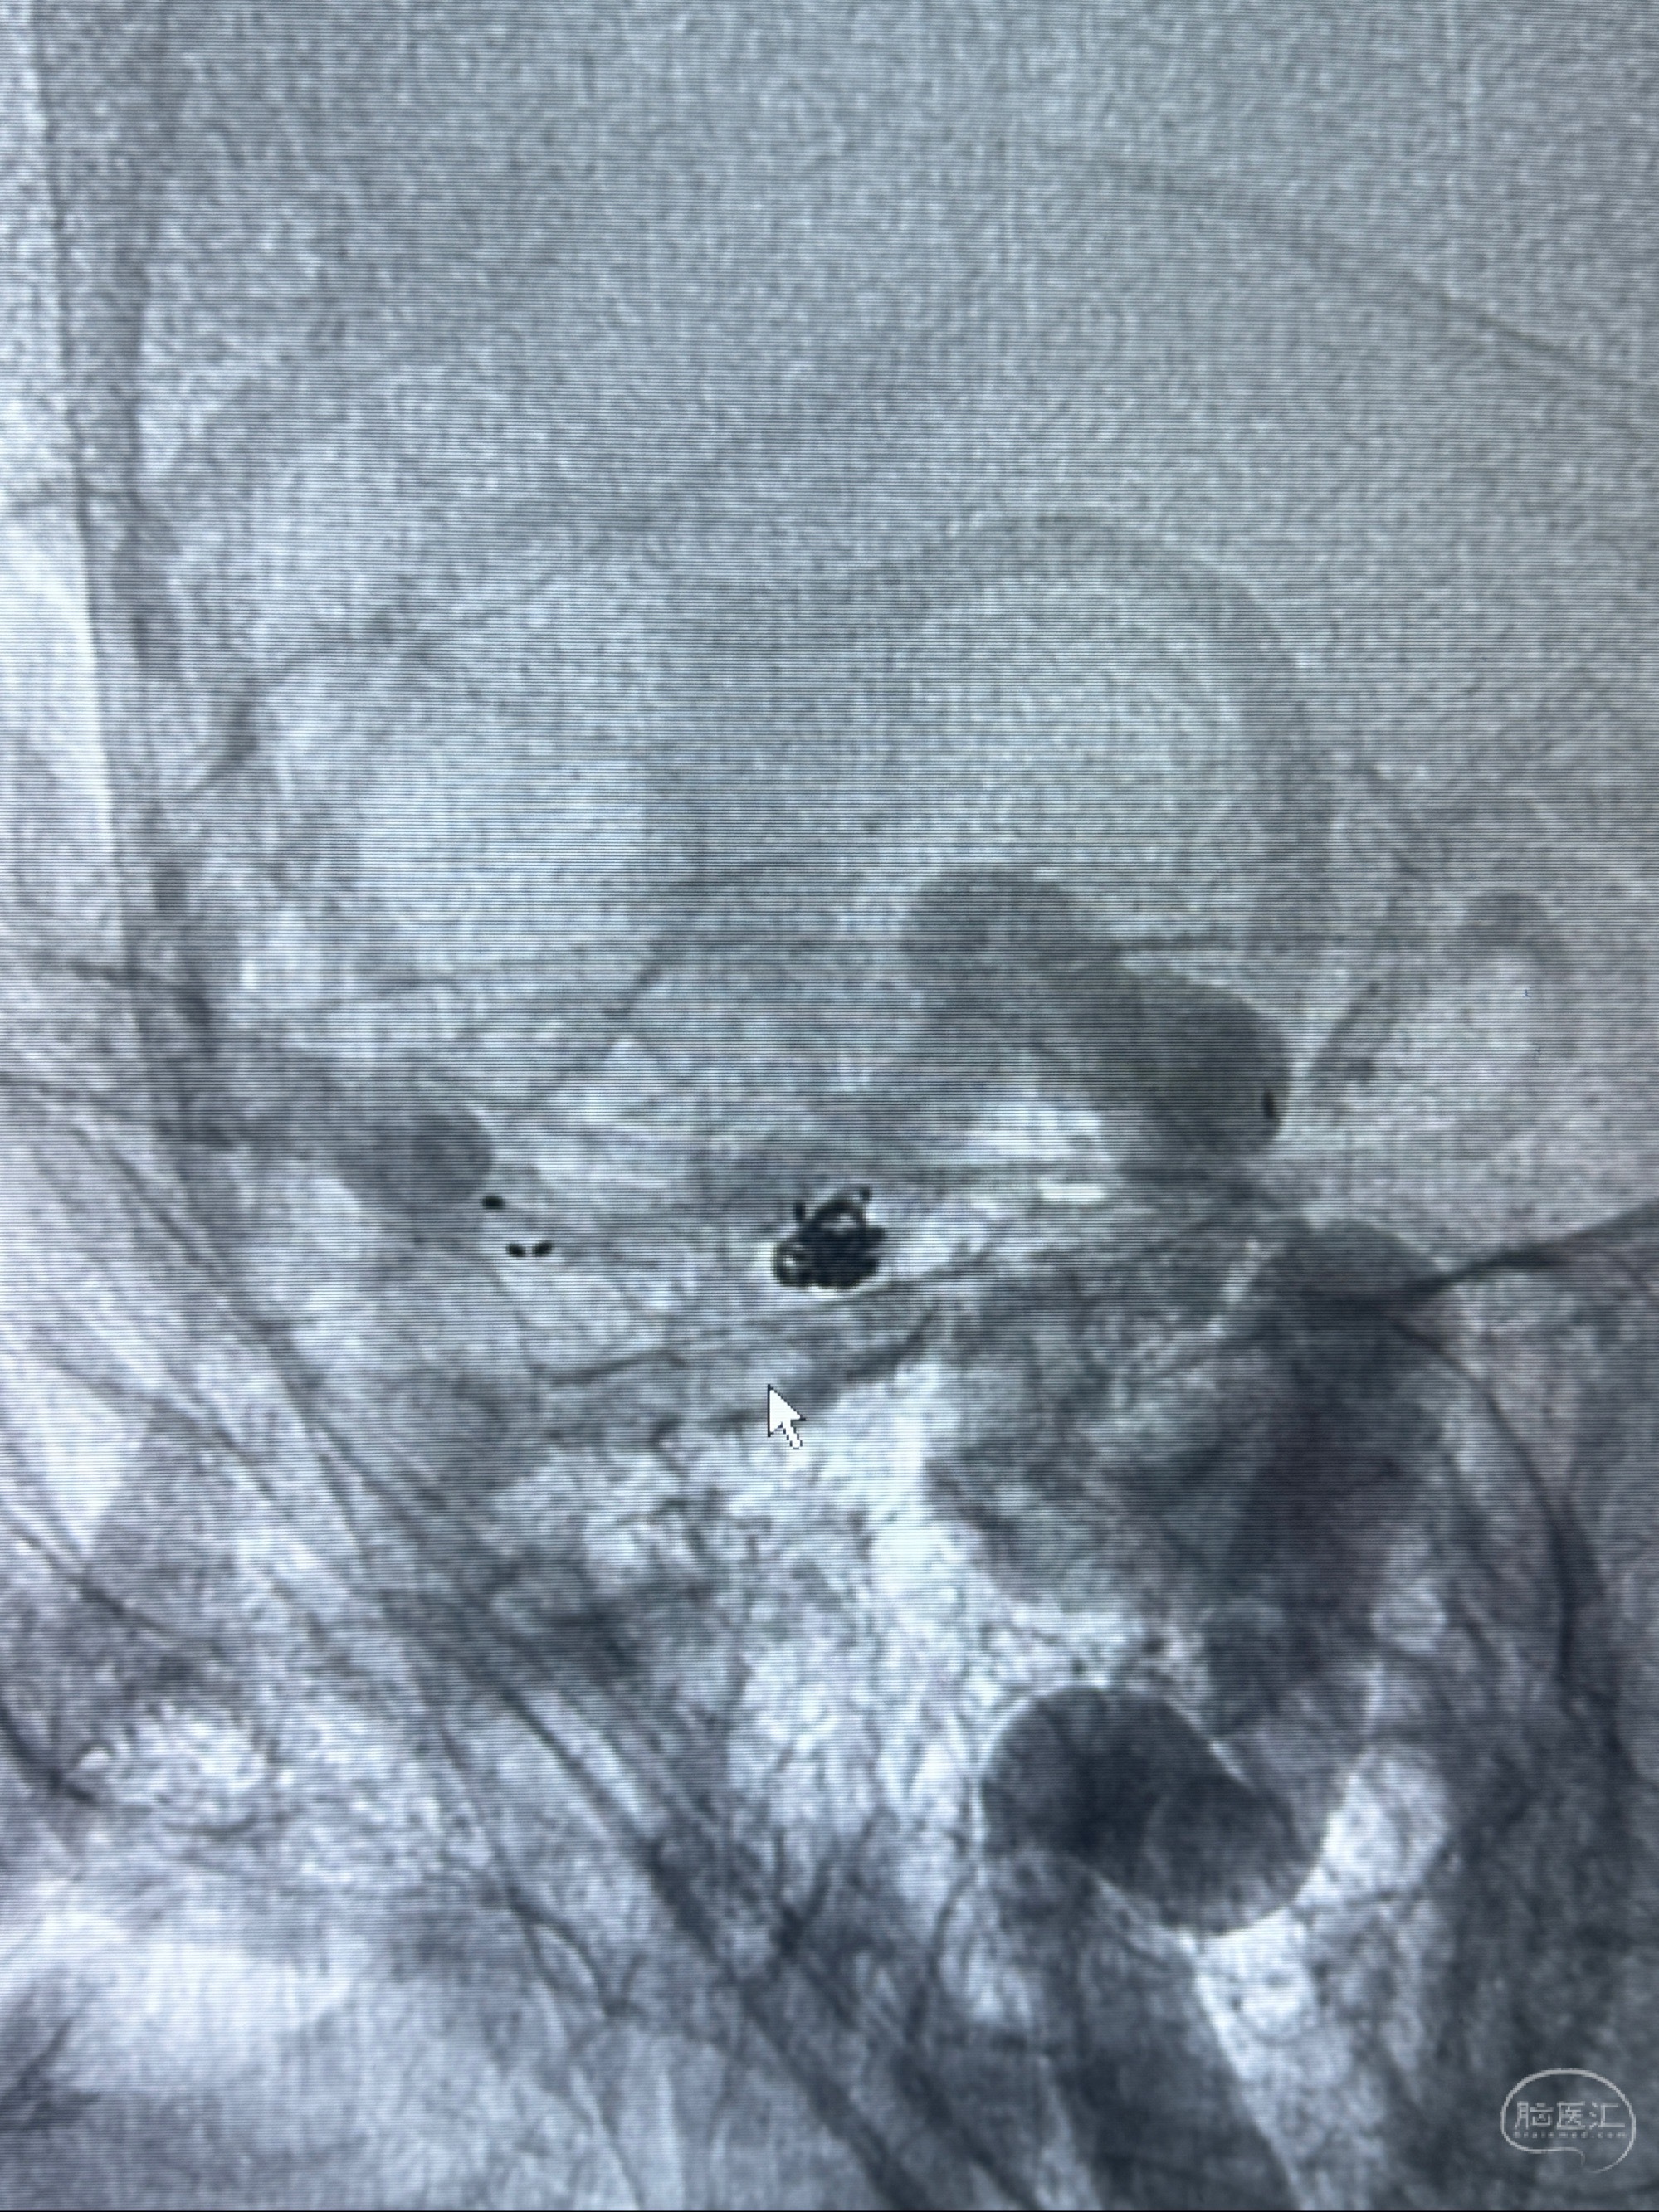

2023-11-24DSA:右侧大脑中动脉下干起始部动脉瘤,约2.3*2.5mm,形态规则

治疗策略:

- 随访?

- 夹闭?

- 单弹簧圈填塞?

- 支架辅助治疗?

2023-12-04全麻下行支架辅助治疗

S-AB4-20mm